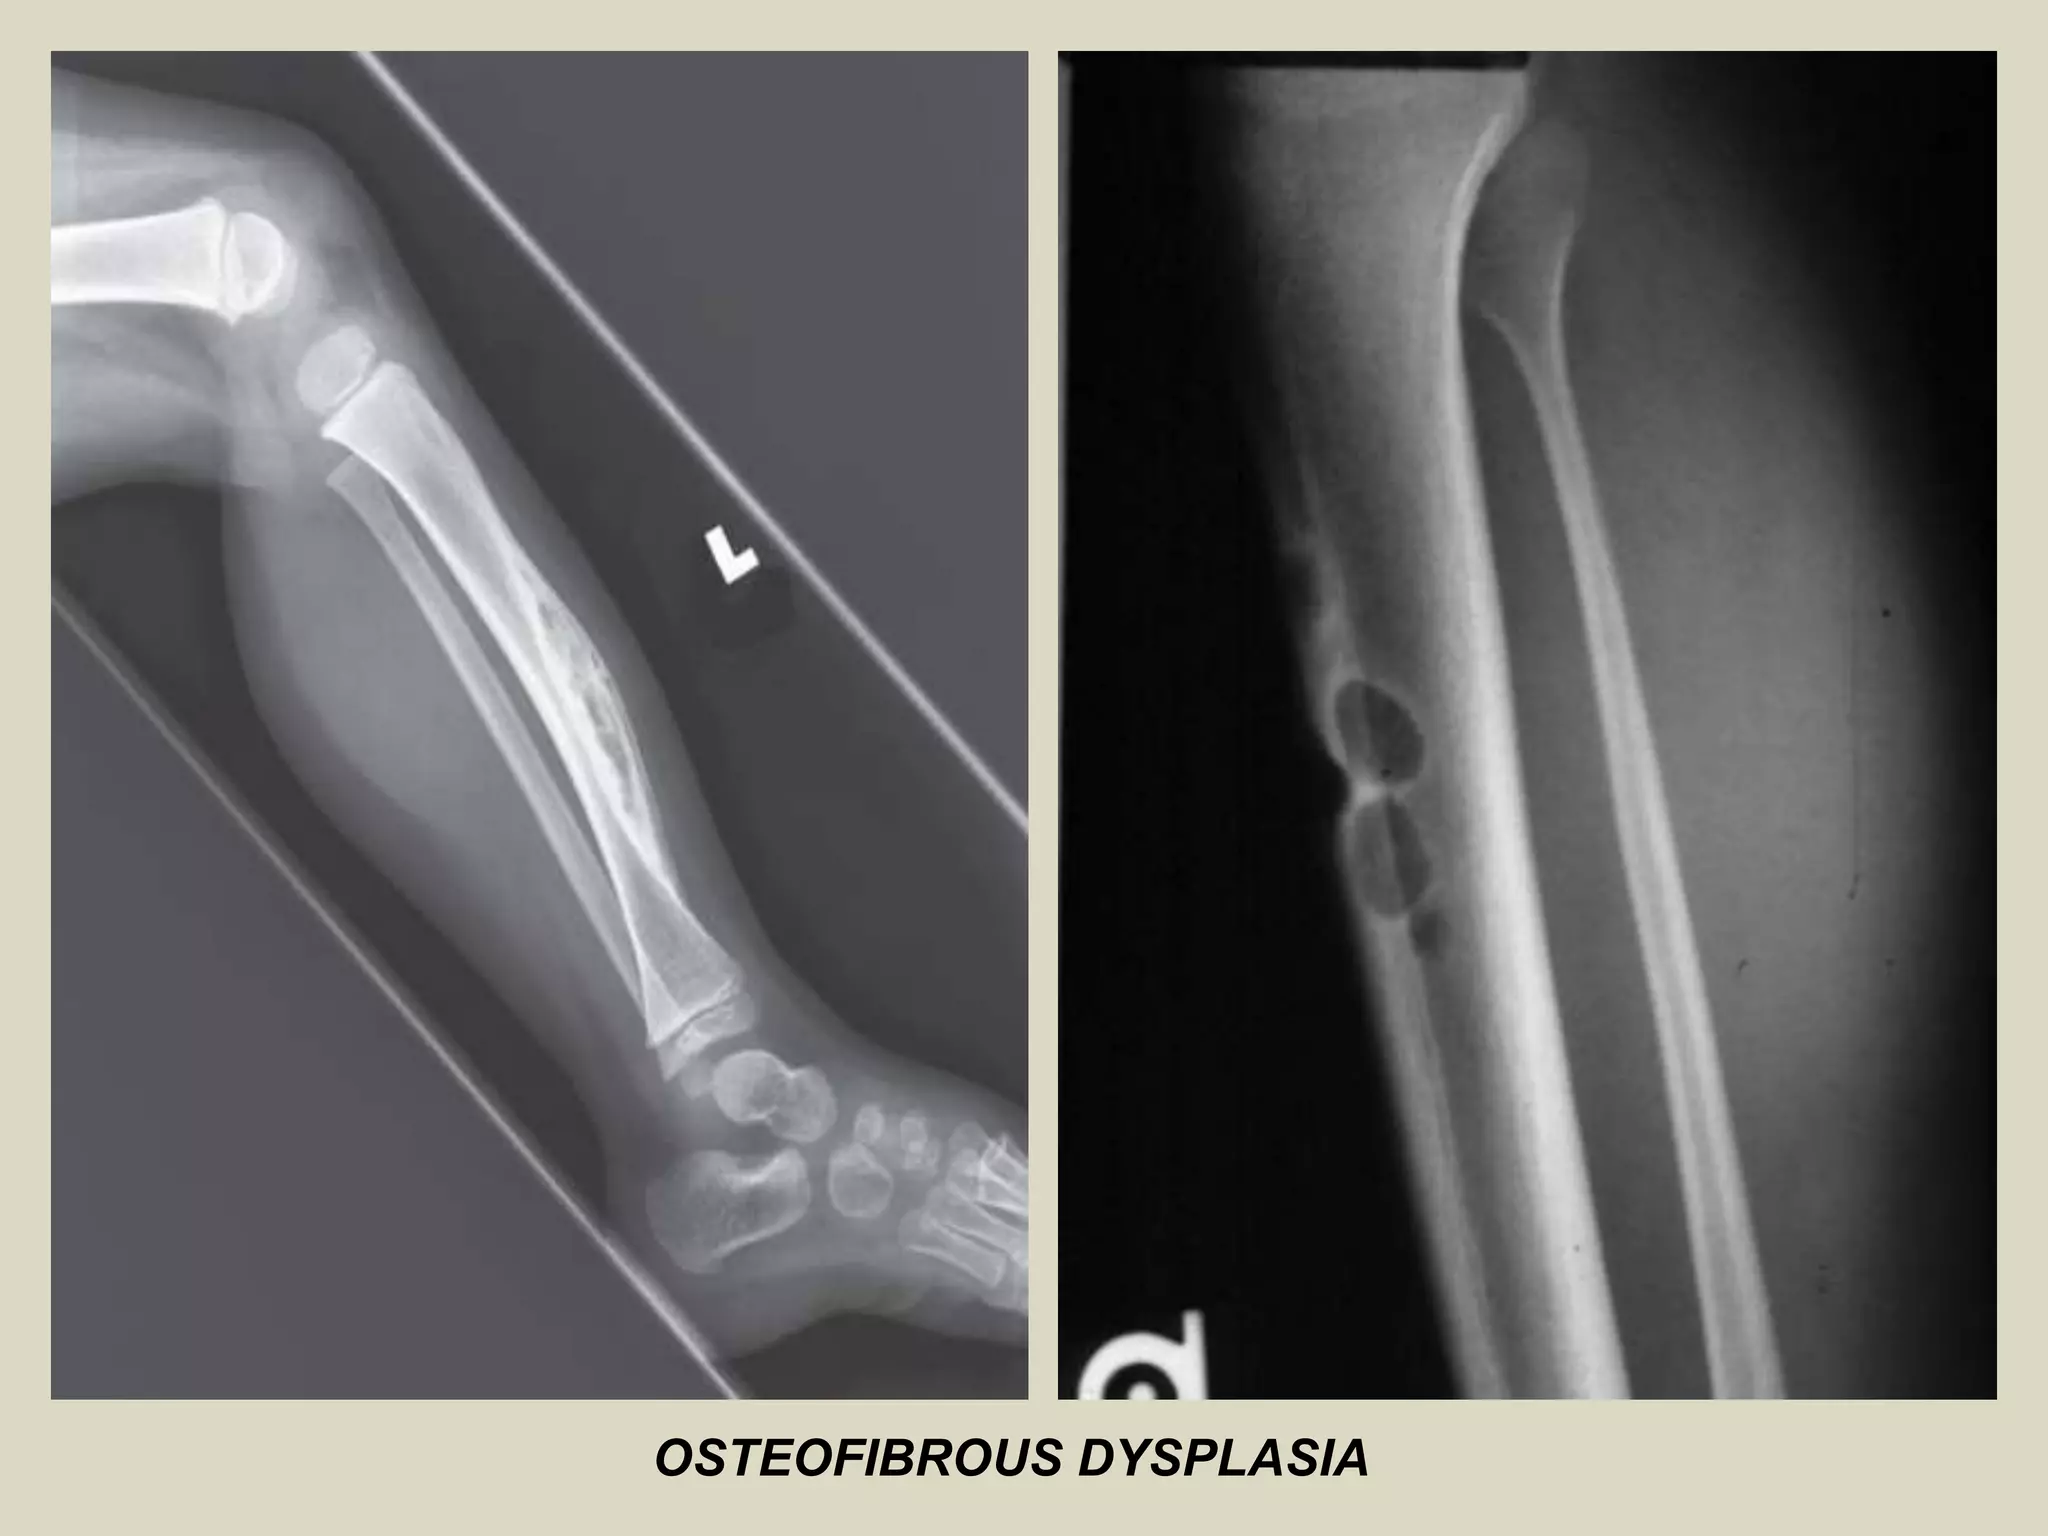

OSTEOFIBROUS DYSPLASIA

Definition:

- Self-limited benign fibro-osseous lesion of bone.

- Involving cortical bone of the anterior mid-shaft of the tibia during infancy and

childhood.

Imaging:

- Well-delineated, Intracortical lucency, surrounded by areas of sclerosis.

- May form as a single lytic lesion, but more commonly forms confluent oval-shaped,

scalloped, saw-toothed or bubbly multiloculated lytic lesions in cortex.

OSTEOFIBROUS DYSPLASIA.